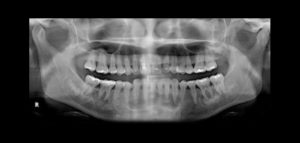

Paciente femenino de 27 años de sexo femenino acude al Instituto de Diagnóstico Maxilofacial para evaluación preoperatoria de cirugía ortognática. A la evaluación de la